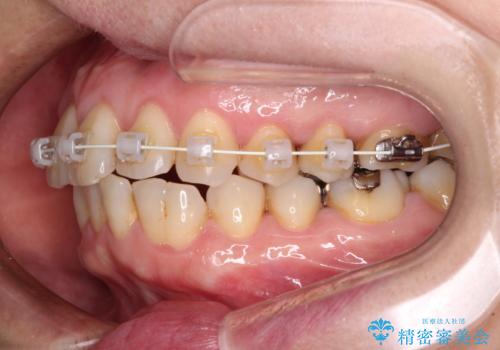

- 矯正装置

- 審美装置

- 治療期間

- 9ヶ月

- 治療回数

- 10-30回